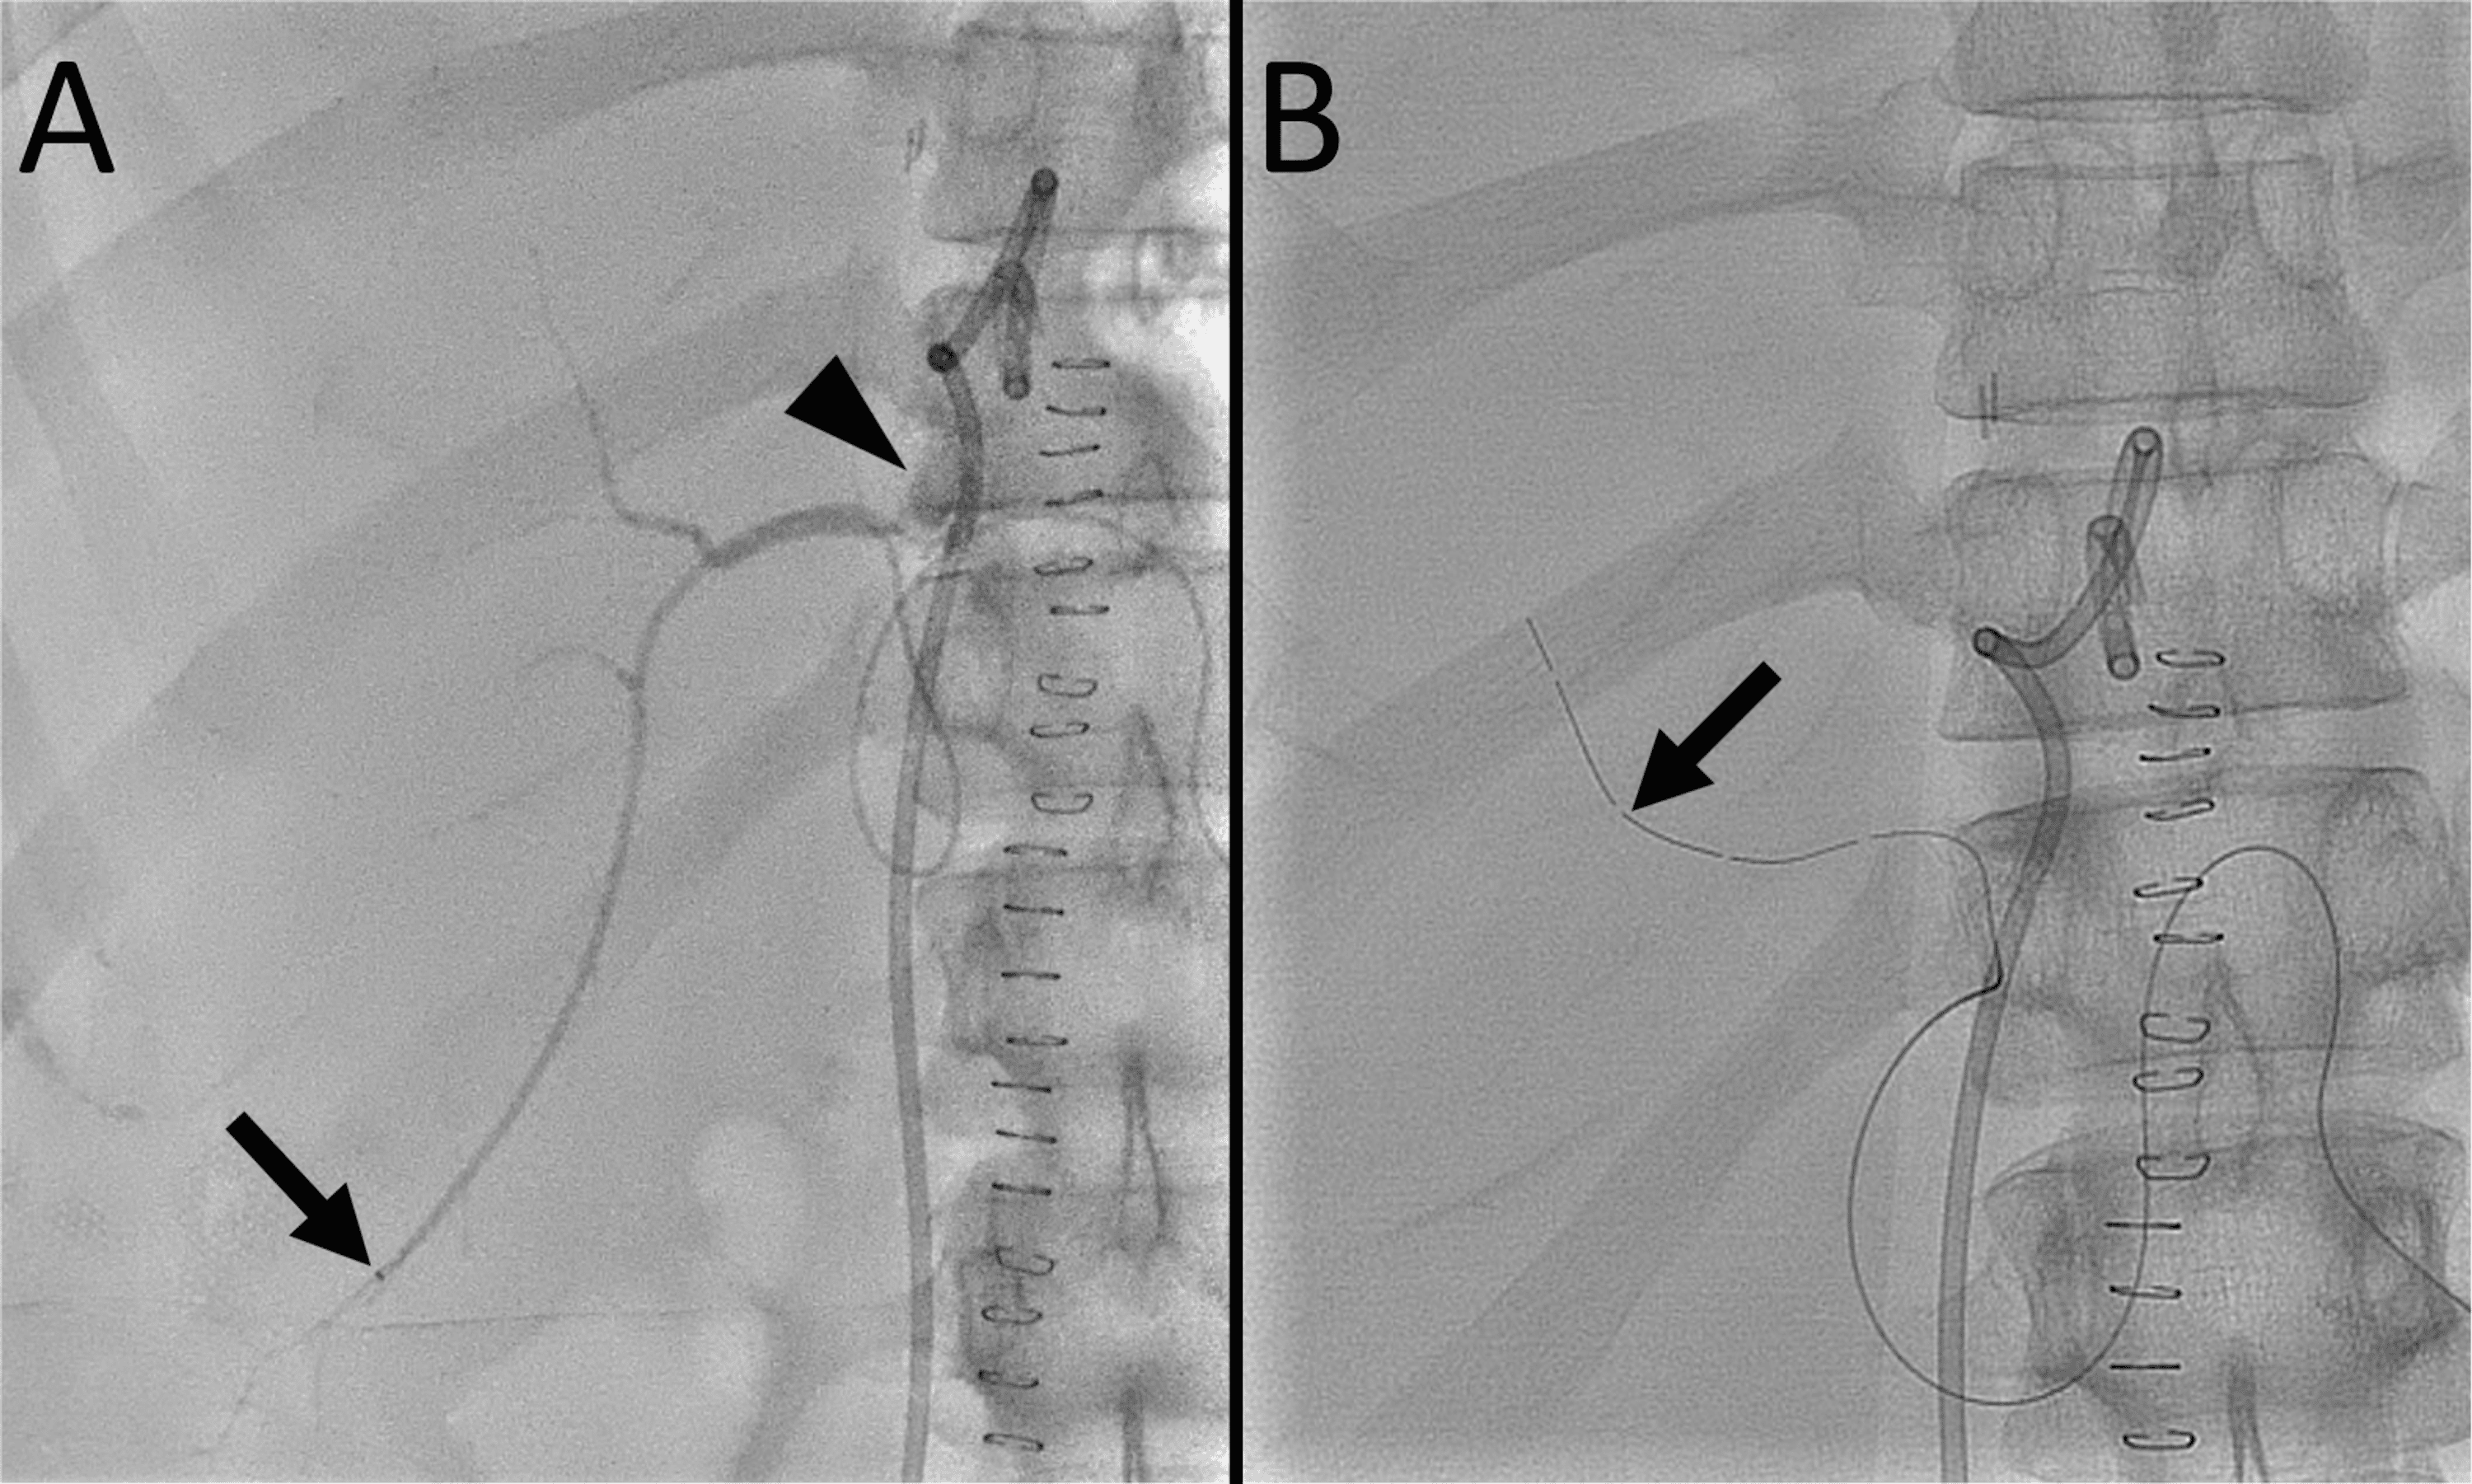

From www.cureus.com

Cureus Dual Lumen Microcatheter in Percutaneous Biliary Drainage for Biliary Drainage Leakage Biliary stenting, endoscopic biliary sphincterotomy, and nasobiliary. — various endoscopic treatments (i.e. Delayed diagnosis is not uncommon due to nonspecific. — bile leaks can be a complication of abdominal surgeries, specifically trauma to the biliary system. — bile leaks can result in significant morbidity and mortality. A total of 1028 patients with a median age of 56. Biliary Drainage Leakage.

Dual Lumen Microcatheter in Percutaneous Biliary Drainage for Biliary Drainage Leakage Delayed diagnosis is not uncommon due to nonspecific. — a bile duct drain, also called biliary drainage, can help treat blocked bile ducts so that bile may flow as it should, helping your liver digest. — bile leaks can be a complication of abdominal surgeries, specifically trauma to the biliary system. A total of 1028 patients with a. Biliary Drainage Leakage.